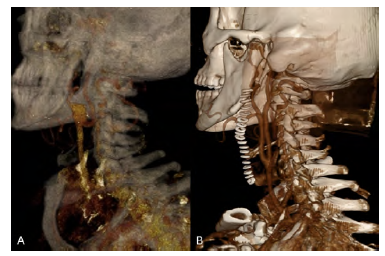

A 60-year-old male with a history of hypertension, dyslipidemia, and atrial fibrillation presented with an asymptomatic 20mm type III aneurysm of the carotid bifurcation (Figure 1A). No aneurysms were found in other vascular territories. He underwent arterial reconstruction with an interposition bypass using a 6mm ePTFE graft with reimplantation of the external carotid artery (ECA) on the graft (Figure 1B). Intraoperative cerebral perfusion monitoring was performed with near-infrared spectroscopy (INVOS™), without significant drop after carotid clamping, thus shunt use was not considered. The prosthetic conduit was chosen to minimize the risk of future aneurysmal degeneration. The patient initiated single antiplatelet therapy with acetylsalicylic acid in the immediate postoperative period, to maintain lifelong. There were no complications after two years of follow-up. Histological findings were compatible with atherosclerotic etiology.

Figure 1 Pre and post-operative computed tomography angiography. A - 3D reconstruction showing a type III carotid bulb aneurysm with involvement of the origin of internal and external carotid arteries; B - Post-operative 3D reconstruction.